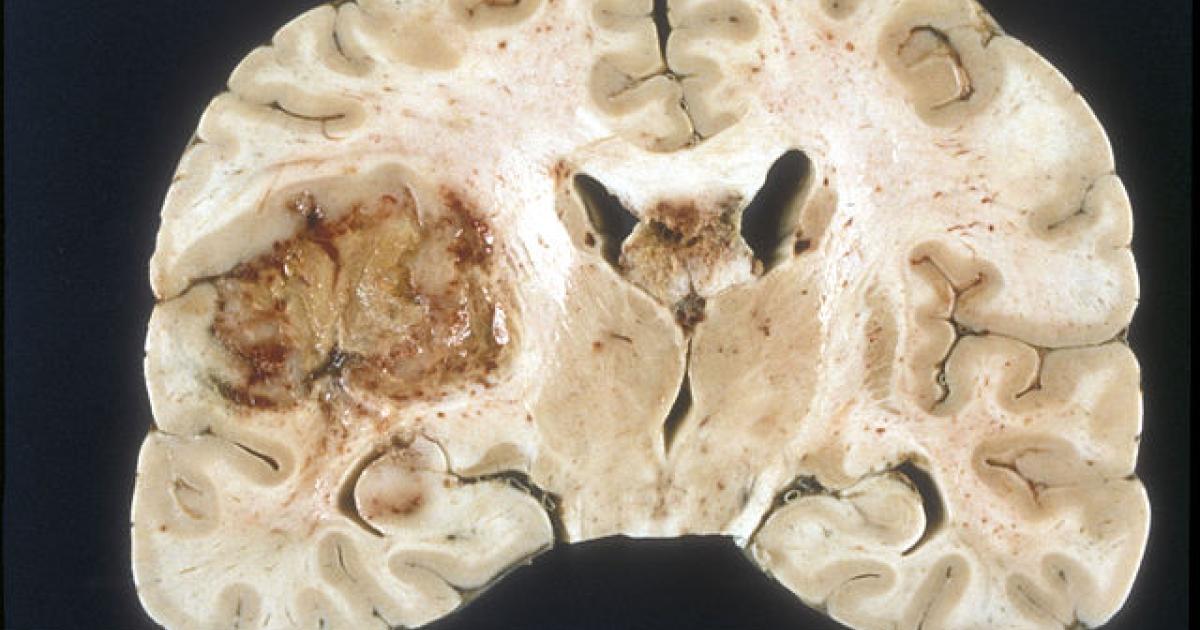

Glioblastoma multiforme (GBM), one of the most dreaded and deadly forms of brain cancer, has been on my mind recently because one of my dog-park friends was recently diagnosed with it. Characterized by aggressive growth and resistance to conventional treatments, GBM affects more than 14,000 Americans and claims approximately 10,000 lives each year. Even with intensive treatment — including surgery, radiation, and chemotherapy — the median survival time after diagnosis is 15 months, and only about five percent of patients survive beyond five years.

GBM's resistance to treatment stems from its complexity and heterogeneity. The tumor is not just one type of cancer cell; it is a collection of diverse cells, each with different characteristics. This heterogeneity allows the tumor to evade therapies targeting a single marker. Efforts to harness the immune system to attack GBM have often been thwarted by the tumor’s ability to adapt and survive. For example, therapies targeting the epidermal growth factor receptor variant III (EGFRvIII) — a key protein often found in GBM cells — have shown only limited success due to the tumor’s variability.

Adding to the challenge, GBM’s location in the brain or spinal cord makes surgical removal difficult, and the blood-brain barrier limits the effectiveness of many drugs because it prevents them from getting to the site of the tumor. Despite decades of research, effective treatment of GBM is rare.